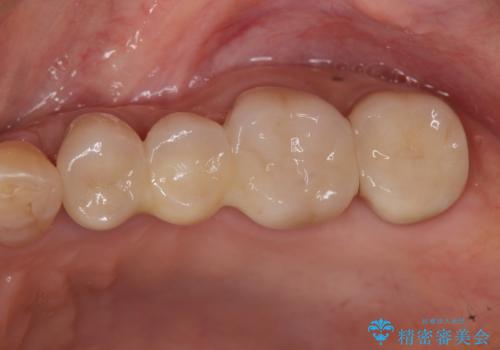

臼歯 咬合の再構成

- 20年前に治療した銀歯が壊れ、審美的な修復を希望され来院されました。

銀歯・虫歯を除去し、ジルコニアを咬合再構成を行います。

- 66万円(仮歯・ジルコニアクラウン×6)費用は治療当時の料金となります